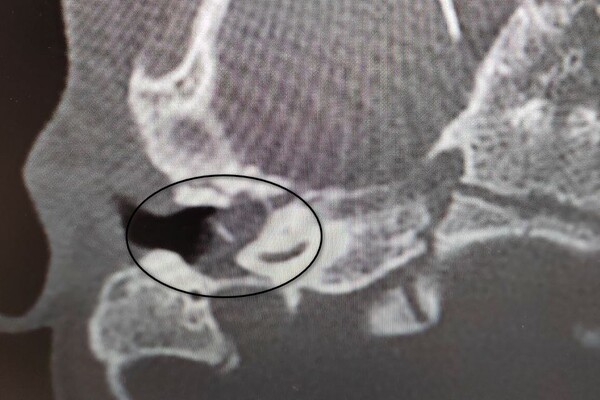

Девочка поступила в оториноларингологическое отделение больницы с хроническим гнойным средним отитом и подозрением на врожденную холестеатому барабанной полости — кистозное патологическое образование в среднем ухе. Врачи отметили, что подобное заболевание крайне редко диагностируется у детей в столь раннем возрасте.

«Холестеатома опасна тем, что может привести к рецидивирующему гноетечению и разрушению структур среднего уха, отвечающих за слух», — пояснили в пресс-службе ведомства.

После обследования и подтверждения диагноза пациентку направили на операцию, в ходе которой хирурги удалили у нее холестеатому, провели декомпрессию лицевого нерва и восстановили механизм звукопроведения.